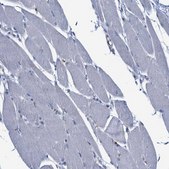

Anti-CCL2 antibody produced in rabbit, a Prestige Antibody, is developed and validated by the Human Protein Atlas (HPA) project . Each antibody is tested by immunohistochemistry against hundreds of normal and disease tissues. These images can be viewed on the Human Protein Atlas (HPA) site by clicking on the Image Gallery link. The antibodies are also tested using immunofluorescence and western blotting. To view these protocols and other useful information about Prestige Antibodies and the HPA, visit sigma.com/prestige.

The Human Protein Atlas project can be subdivided into three efforts: Human Tissue Atlas, Cancer Atlas, and Human Cell Atlas. The antibodies that have been generated in support of the Tissue and Cancer Atlas projects have been tested by immunohistochemistry against hundreds of normal and disease tissues and through the recent efforts of the Human Cell Atlas project, many have been characterized by immunofluorescence to map the human proteome not only at the tissue level but now at the subcellular level. These images and the collection of this vast data set can be viewed on the Human Protein Atlas (HPA) site by clicking on the Image Gallery link. We also provide Prestige Antibodies® protocols and other useful information.

• IHC tissue array of 44 normal human tissues and 20 of the most common cancer type tissues.